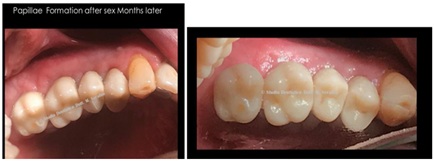

Control at six months on the right side and at 14 months on the left side, after finalization (Figure 27).

Figure 27: Control at six months on the right side and at 14 months on the left side.

Control two months after loading on the right side and sixteen months on the left side (Figure 29).

Figure 29: Control two months after loading on the right side and sixteen months on the left side.

Final result with one-to-one fixed prosthesis in lithium disilicate with formation of papillae and orange peel mucosa (Figure 32).

Figure 32: Formation of papillae and orange peel mucosa.